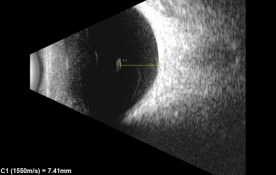

- B-scan ultrasound: Ultrasound can be used to image opacities within the vitreous body. Quantitative ultrasonography of the vitreous provides a measure of floater severity.[22] [23]It is also used as the main method for determining the location of the opacity in relation to the retina and lens.